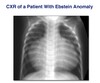

-CXR of pt with ebstein anomaly -massive cardiomegaly - box shape appearance -due to right atrial enlargement -right atrial hypertrophy -right side megaly = rotational changes in heart of RV or RA hypertrophy -left side megaly = LV hypertrophy -flat LA = LA hypertrophy -nike swoop on top left = normal